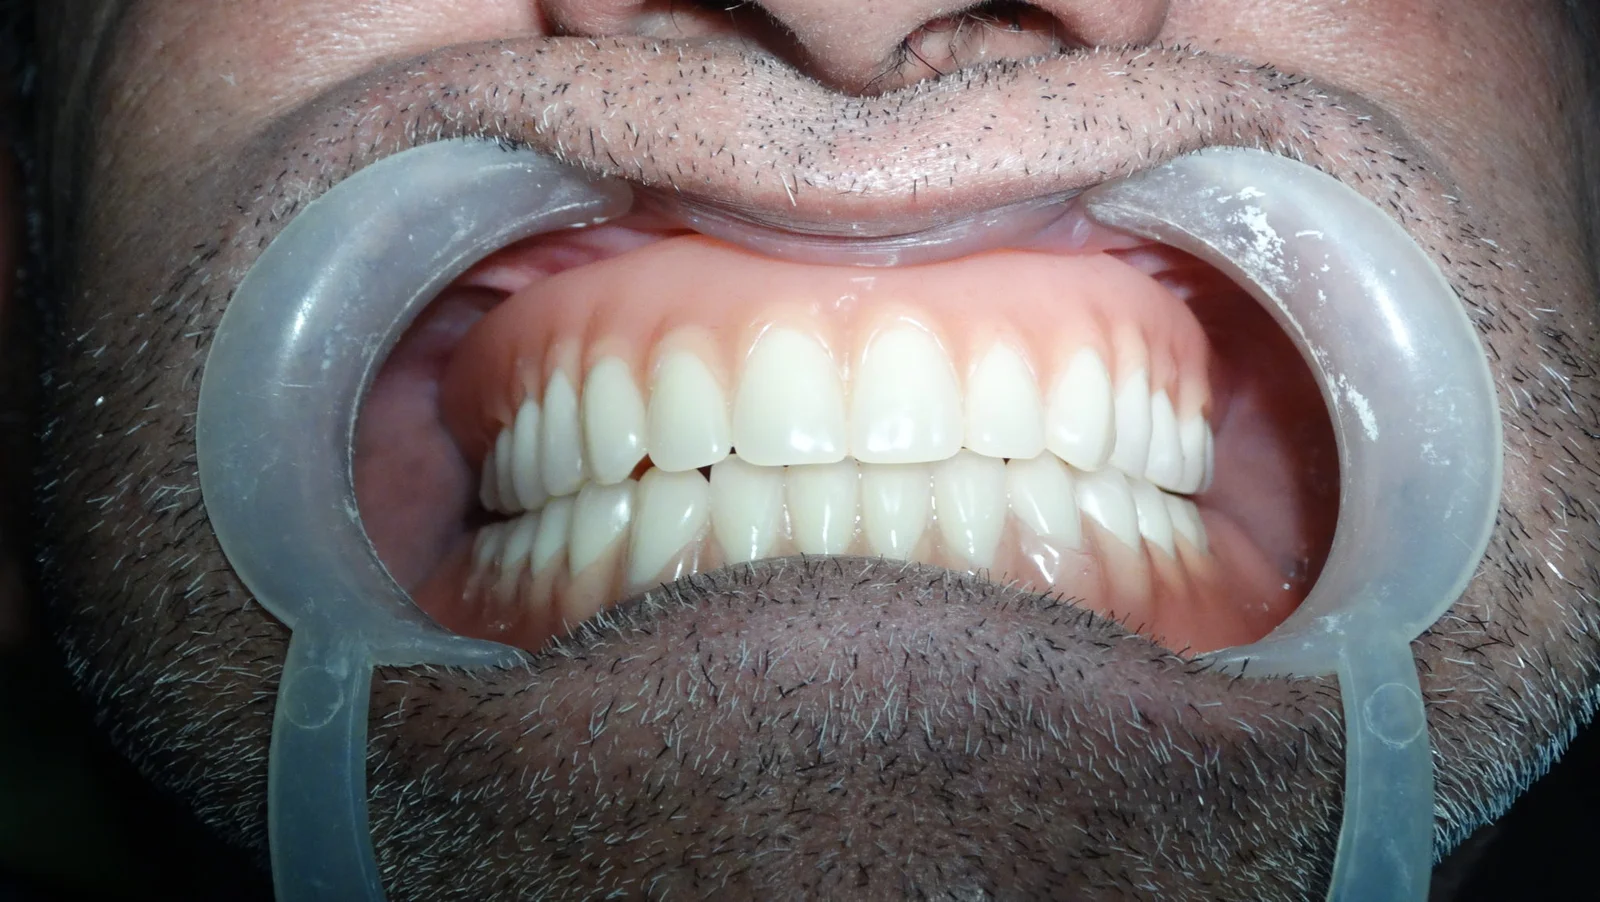

Clinical Case Progression

Full Mouth Rehabilitation

Implant Supported Fixed Teeth

Replacing all missing teeth with a permanent, fixed prosthesis that mimics the look, feel, and function of natural teeth. Explore our clinical transformations below.